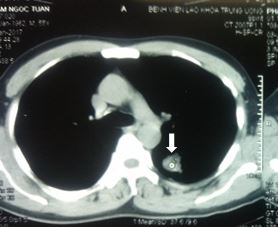

Tiền sử; khỏe mạnh, không hút thuốc. Các xét nghiệm khác trong giới hạn bình thường, chỉ số CEA 56 ng/ml. Chụp CT scanner Lồng ngực phát hiện u phổi trái.

Hình 1: Hình ảnh CT ngực có khối u phổi trái kích thước 2 cm, ngấm thuốc cản quang